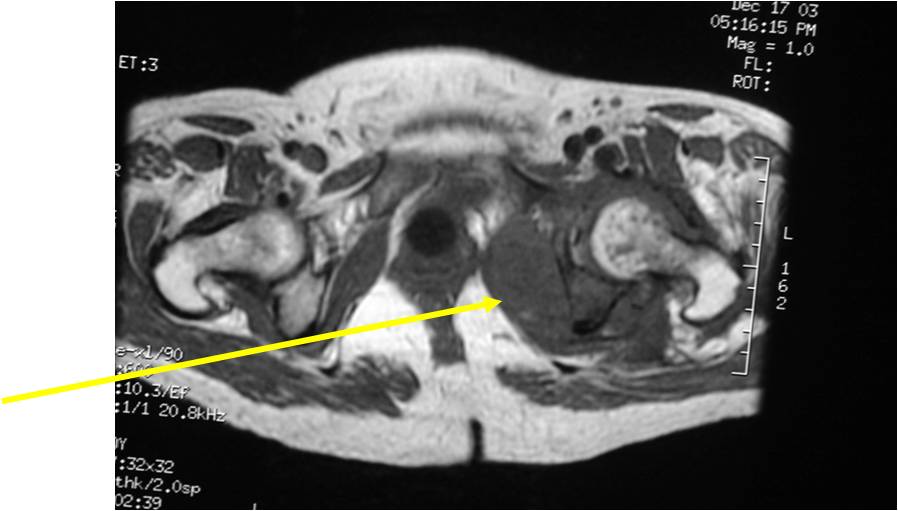

Radiology emulates pathology: Biphasic Tumor

- One region low grade chondrosarcoma

- Second more aggressive area with bone destruction, lysis of calcification, soft tissue mass

- Cortical permeation and a soft tissue mass in 70% of cases

Ill-defined, lytic intraosseous lesion

- Or extraosseous soft tissue mass

- Devoid of calcifications in continuity with lesions having the features of a cartilaginous tumor

Characteristically abrupt transition between chondroid tumor and dedifferentiated, lytic component

Bone may be expanded and adjacent cortex thickened

(Right Arrow)Aggressive Lytic Area (Dedifferentiated Sarcomatous Component) Cortical Destruction Soft Tissue Mass without Calcification